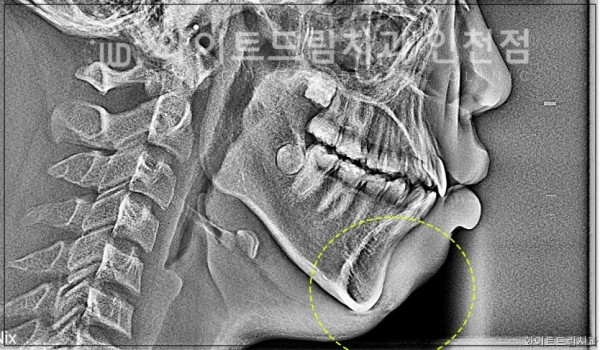

돌출입과 무턱은 2급 부정교합에서 흔히 나타나는 증상으로,

상악이 과도하게 성장했거나, 하악이 충분히 성장하지 않아 발생합니다.

특히 동양인에서 자주 나타나는 얼굴 형태 중 하나입니다.